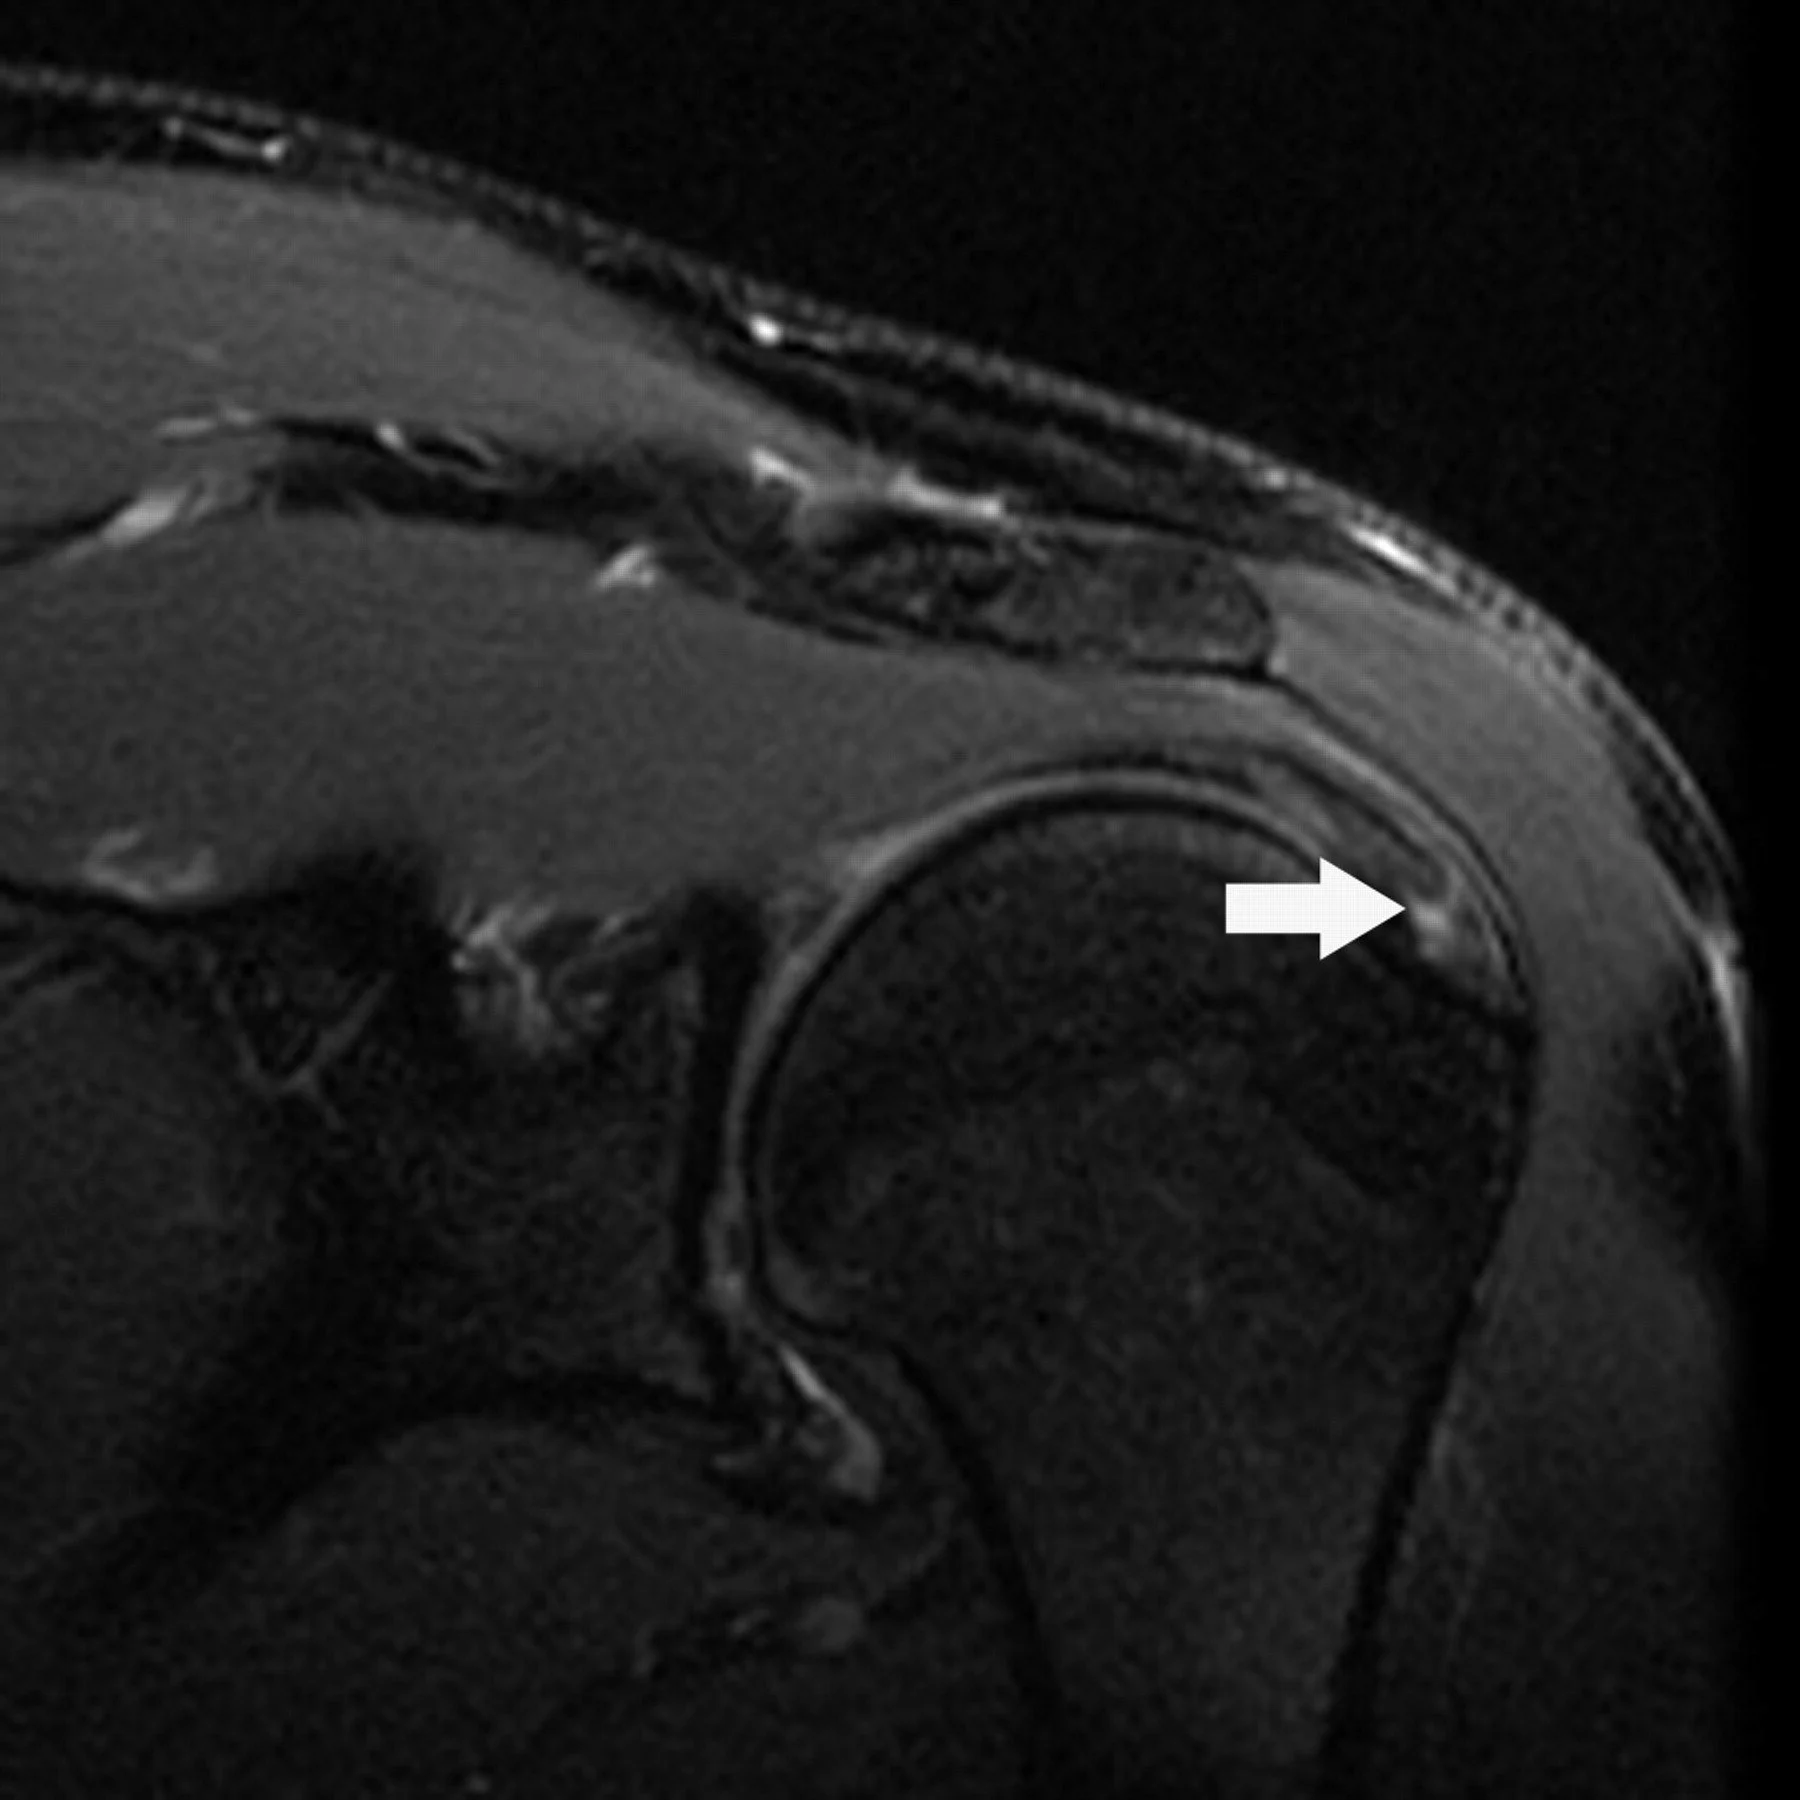

Partial-thickness articular-sided supraspinatus tendon tear on MRI. Image courtesy of Magee et al., AJR, 2006.

• Articular-Sided: This specific study looked at "articular-sided" tears, which means the fraying is happening on the inner side of the tendon, where it faces the shoulder joint.